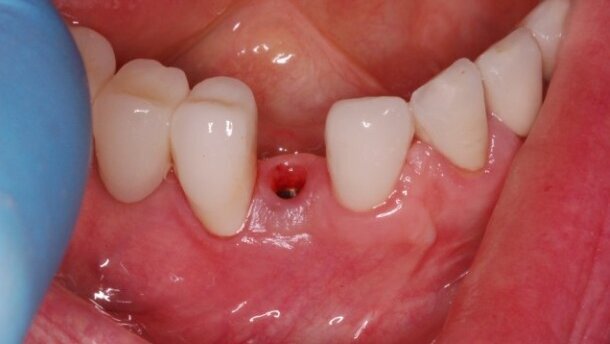

Ryciny pokazują sytuację po odsłonięciu implantu i 2-tygodniowym okresie gojenia z wykorzystaniem śruby gojącej. Na implancie wykonano koronę tymczasową z kompozytu, co umożliwiło jej łatwą modyfikację w gabinecie. Stwierdzono prawie 2 mm recesję dziąsła oraz brak brodawek dziąsłowych przy zębach sąsiednich.

Przez kolejne 12 tygodni modyfikowano koronę tymczasową. Przez pierwsze 2 tygodnie dodawano niewielkie ilości materiału celem kompresji tkanki dziąsłowej wokół implantu. Następnie stopniowo usuwano materiał, wytwarzając miejsce na napełzanie tkanki dziąsłowej wokół korony. Czynność taką wykonywano raz w tygodniu. Proces nadpełzania brodawki w przestrzenie pomiędzy koronami jest widoczny, zależy jednak w głównej mierze od istnienia podparcia kostnego przy sąsiednich filarach oraz odpowiedniego położenia punktów stycznych.

Na rycinach przedstawiono sytuację kliniczną w 18 miesięcy po wykonaniu implantacji – widoczne są w pełni uformowane brodawki dziąsłowe wokół implantu.